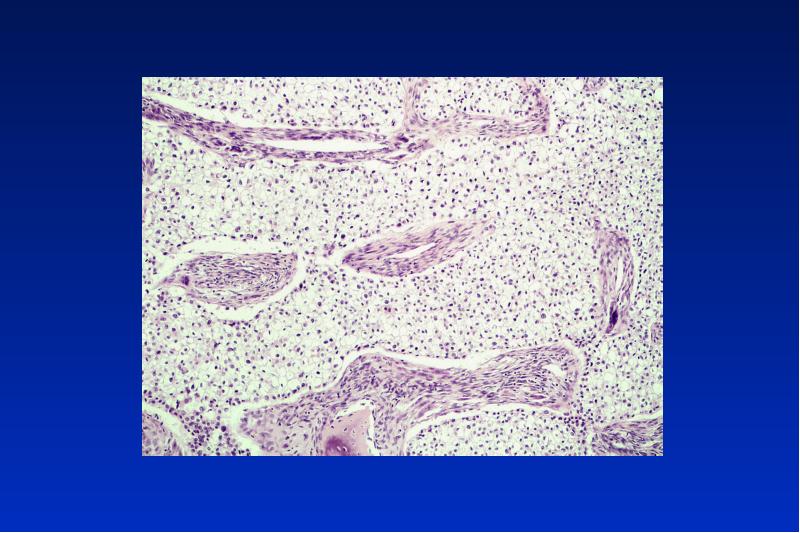

- 77. Periapikale zemento-ossäre Dysplasie benigne nicht neoplastische selbst limitierende Läsion ohne Kapsel